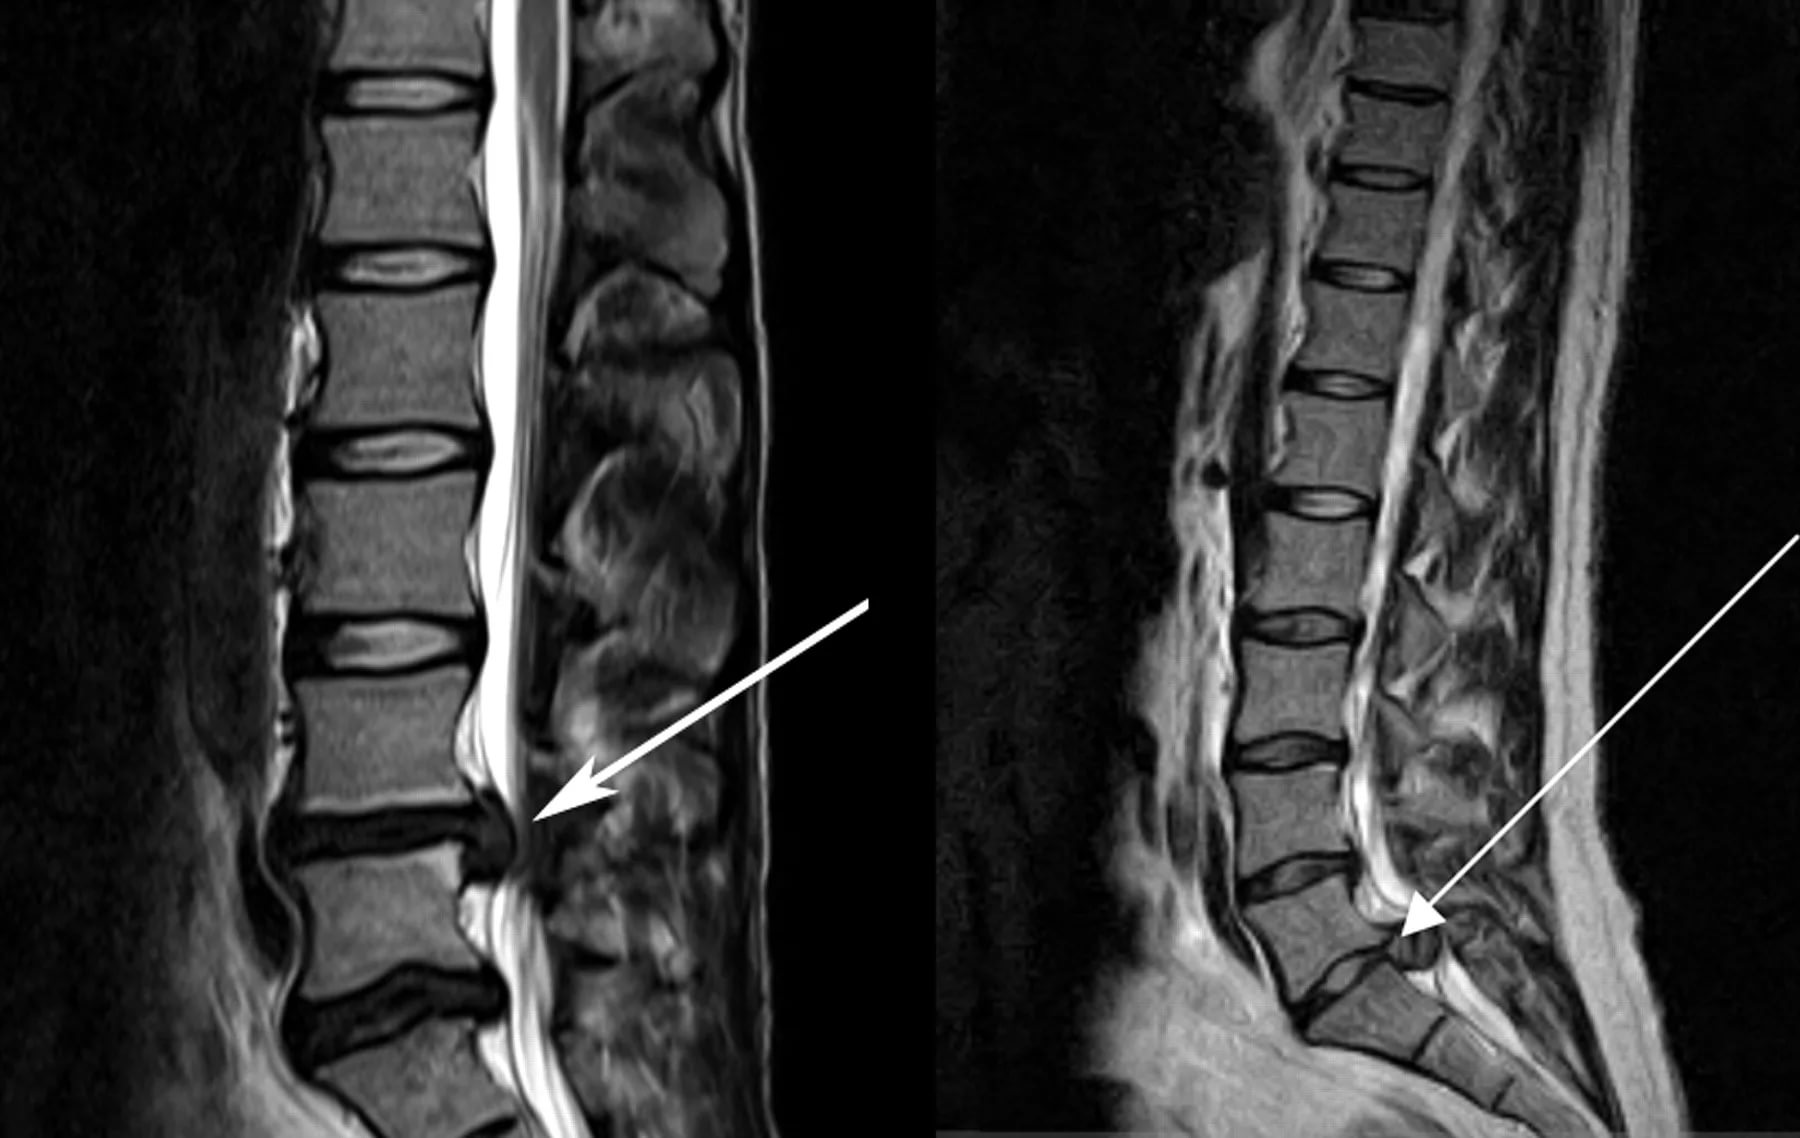

- Рентгенограмма позволяет визуализировать косвенные признаки остеохондроза – сближение позвонков. Но состояние ткани межпозвоночного диска не отражает – для этого дополнительно назначаются КТ, МРТ. Этими же методами удается диагностировать радикулит;

- Защемление нерва определяется по результатам электронейрограммы, МРТ, КТ. Мануальный осмотр также бывает достаточно информативен, ведь компрессия способна вести к снижению рефлексов, чувствительности;

Для выявления различной этиологии новообразований в спинном мозге, позвоночнике, мягких тканях проводят магнитно-резонансную и компьютерную томографию.

Для обнаружения врожденных патологий и новообразований различной этиологии выполняют компьютерную и магнитно-резонансную томографию.